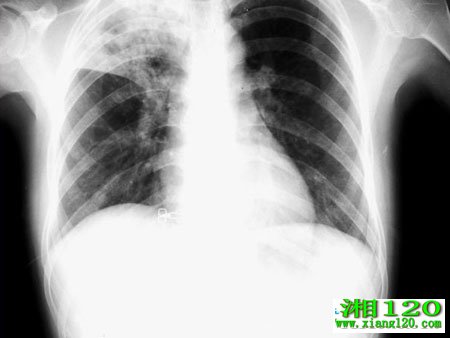

肺炎是高发于儿童身上的常见疾病,危险系数非常大,全世界每年都有很多5岁以下因感染肺炎致死的儿童,该病也被认为是儿童因病致死的首因。其实治疗肺炎并不困难,最难的是如何去发现肺炎,很多父母将儿童咳嗽归结为感冒发烧,并不曾想是病毒或细菌侵入导致支气管发炎或者肺炎,等到发现之时再去医治难度就会增加很多。

如何发现小儿肺炎。2个月以下的孩子如果出现吃奶困难、惊厥、嗜睡或体温上升;2个月~5岁以下的孩子不能喝水,惊厥,嗜睡或不易唤醒,哪些就需要警惕肺炎的可能性,应立即送医,不得延误。

2个月以下的孩子严重胸凹陷加上呼吸增快(≥60次/分)即可判断为重度肺炎。2个月~5岁以下的儿童看到胸凹陷即可判断为重度肺炎;看到呼吸增快即可判断为轻度肺炎。